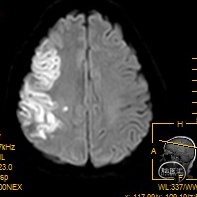

术前MRA显示右侧大脑中动脉远端变窄并分支稀疏。

术后24小时复查颅脑MR未见明显出血。